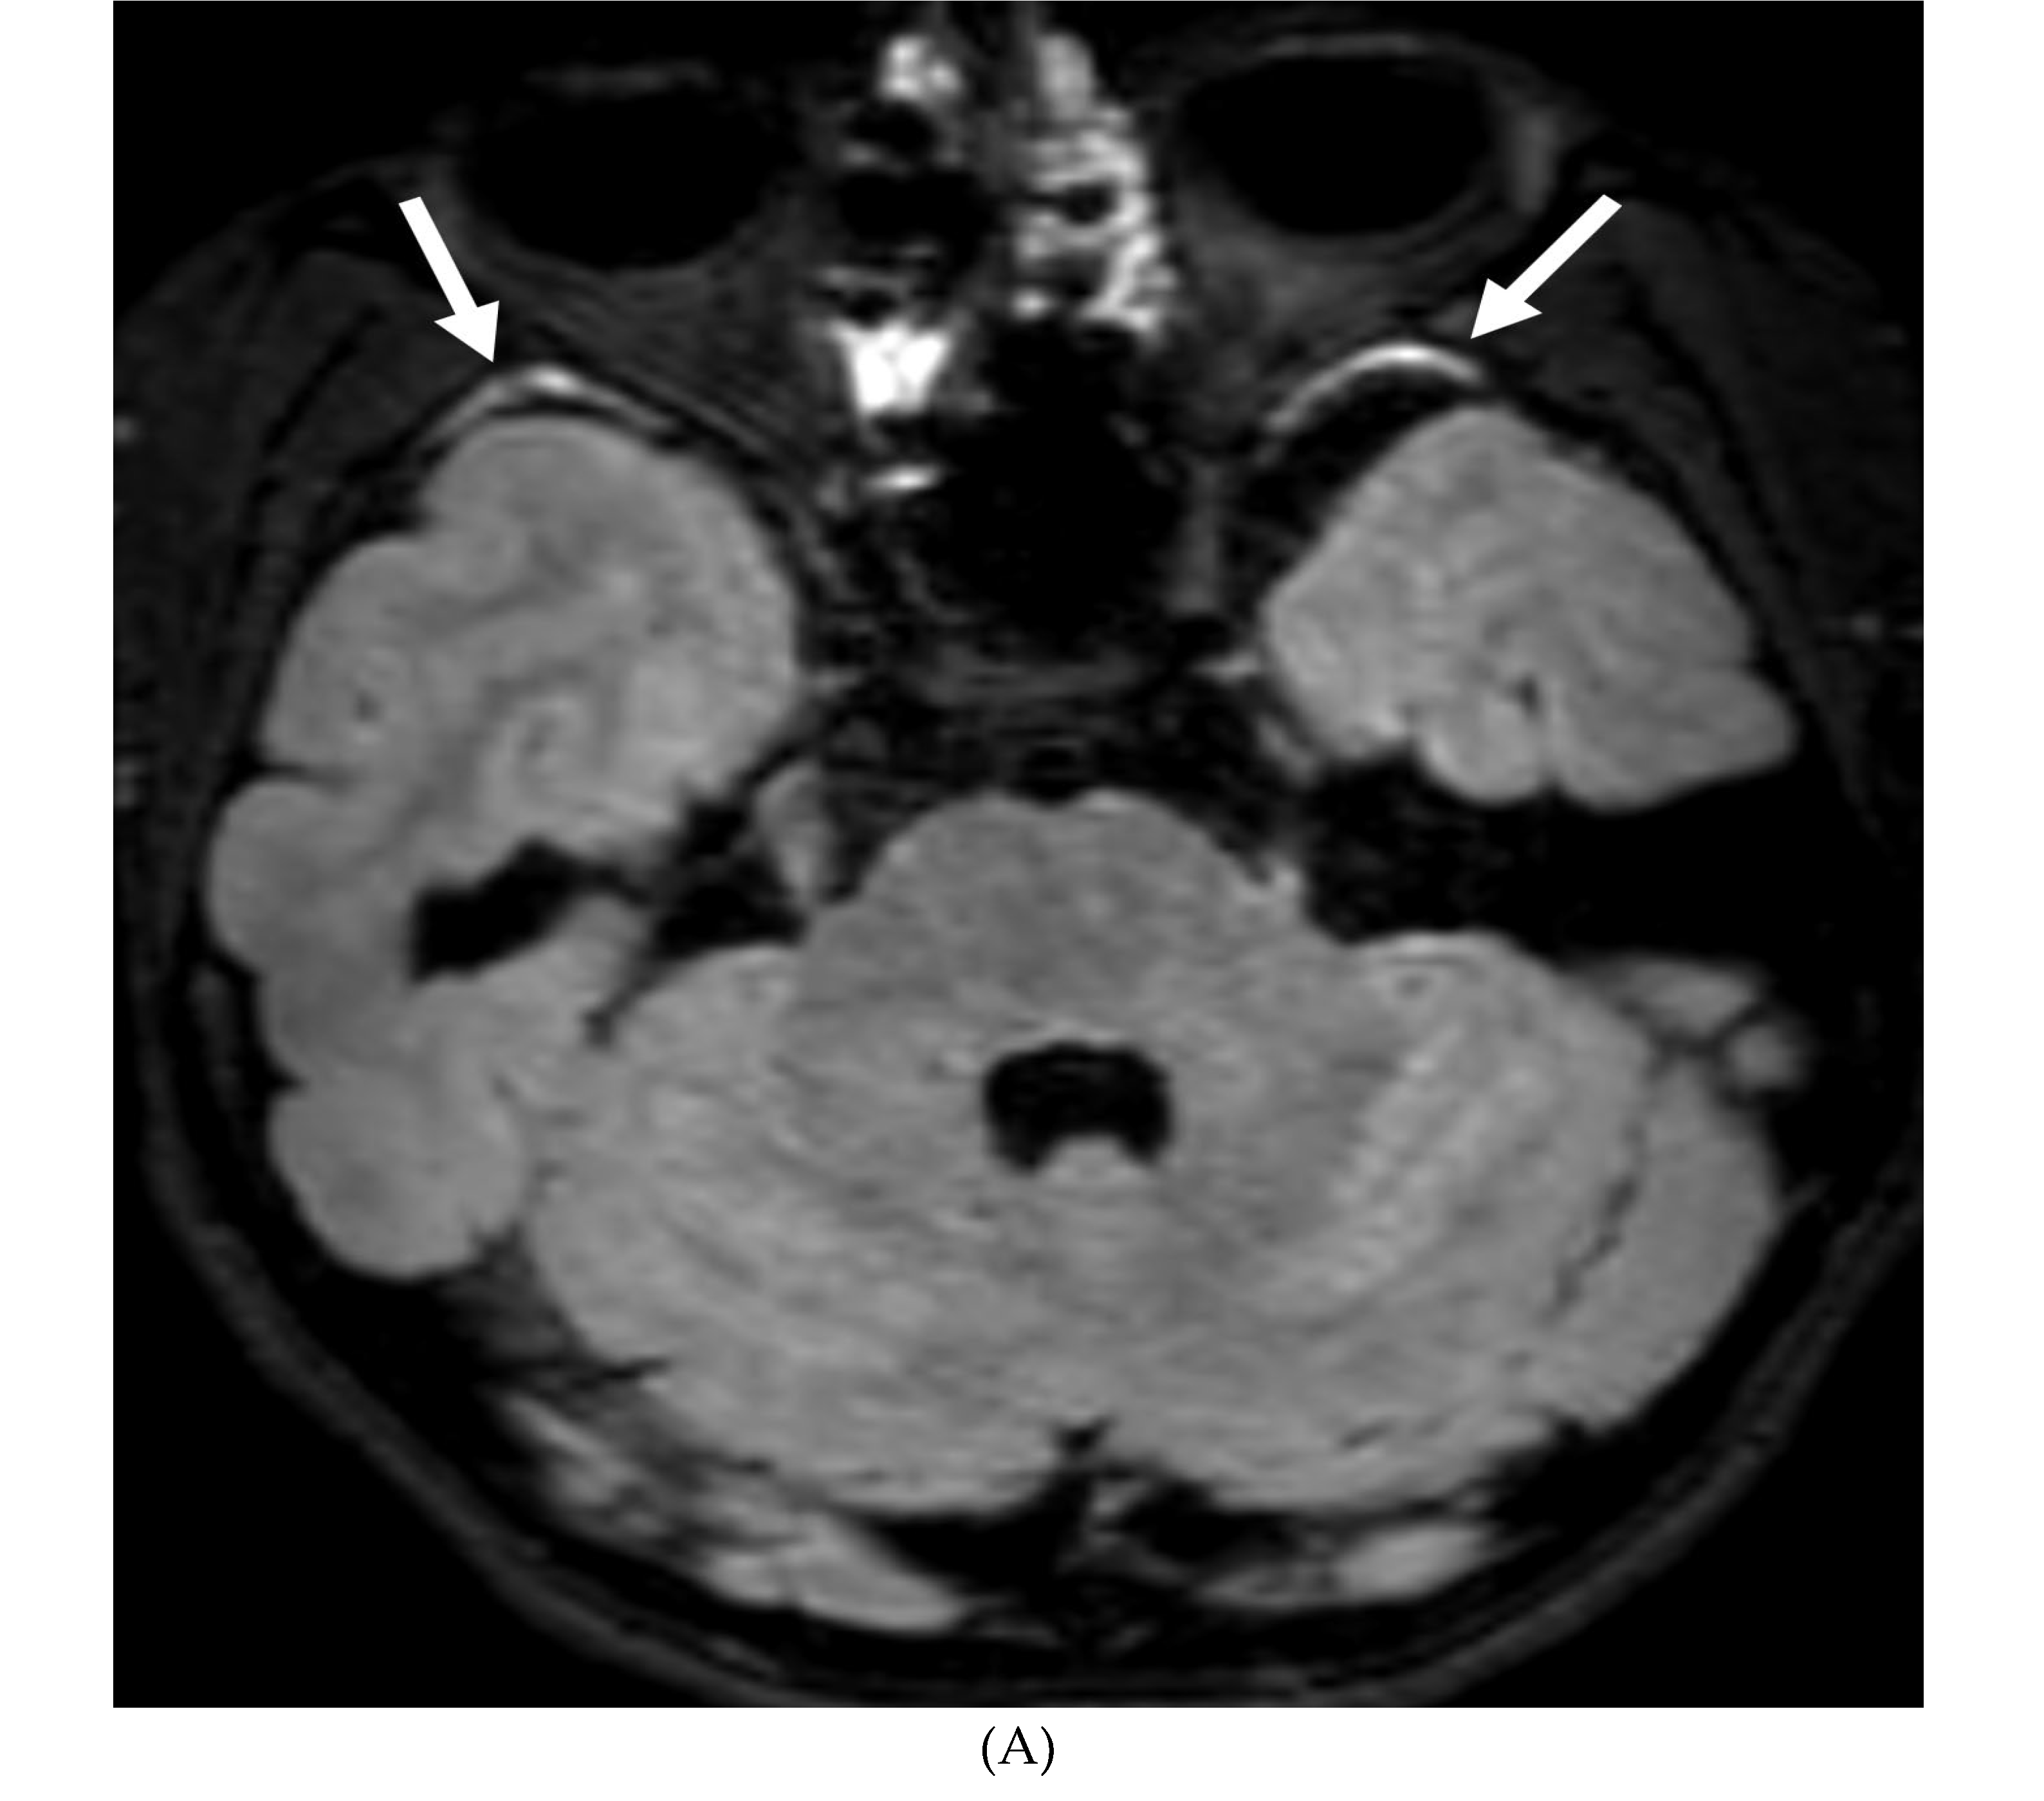

FUNGAL MENINGITIS